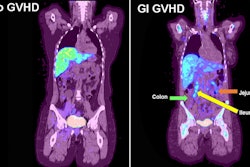

Finally, we noted a study by a group at the University of Oklahoma Health Sciences Center in Oklahoma City that showed that F-18 fluorothymidine PET can visualize early acute gastrointestinal graft versus host disease after patients undergo bone marrow transplants.